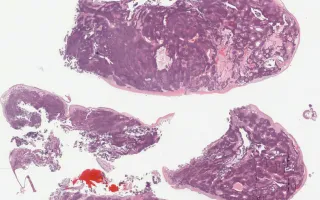

50 year-old female presenting with nasal mass.

Olfactory neuroblastoma, or esthesioneuroblastoma, is an important entity to be considered in the differential diagnosis of lesions of the nasal cavity. This is a malignant neoplasm of neuroectodermal origin, typically arising from the upper part of the nasal cavity. There is a bimodal age distribution, with the lesion typically affecting those between 10-20 years and 50-60 years. Clinically, patients present with obstructive symptoms, headaches, epistaxis, and nasal pain.

Histologically, it is characterized as a lesion consisting of uniform cells with a lobular pattern of growth. Pseudorosettes (Homer Wright) and true rosettes (Flexner-Wintersteiner) can be identified. By immunohistochemistry, these lesions show positive staining for neuroendocrine markers, and S100 and GFAP can be used to highlight sustentacular cells which line the lobules. Histologic grade is determined by the Hyams criteria, which include architecture, mitotic activity, nuclear pleomorphism, presence of a fibrillary matrix, type of rosettes, and presence of necrosis - these factors are then used to assign a grade of 1-4. Given the presence of scattered mitoses and nuclear atypia in this case, it was assigned a grade of 2/4. By immunohistochemistry, this case demonstrated positive staining for synaptophysin and other neuroendocrine markers, as well as S100 staining in the sustentacular cells.

This slide shows H&E stain. See Related Content for synaptophysin and S100 stains.